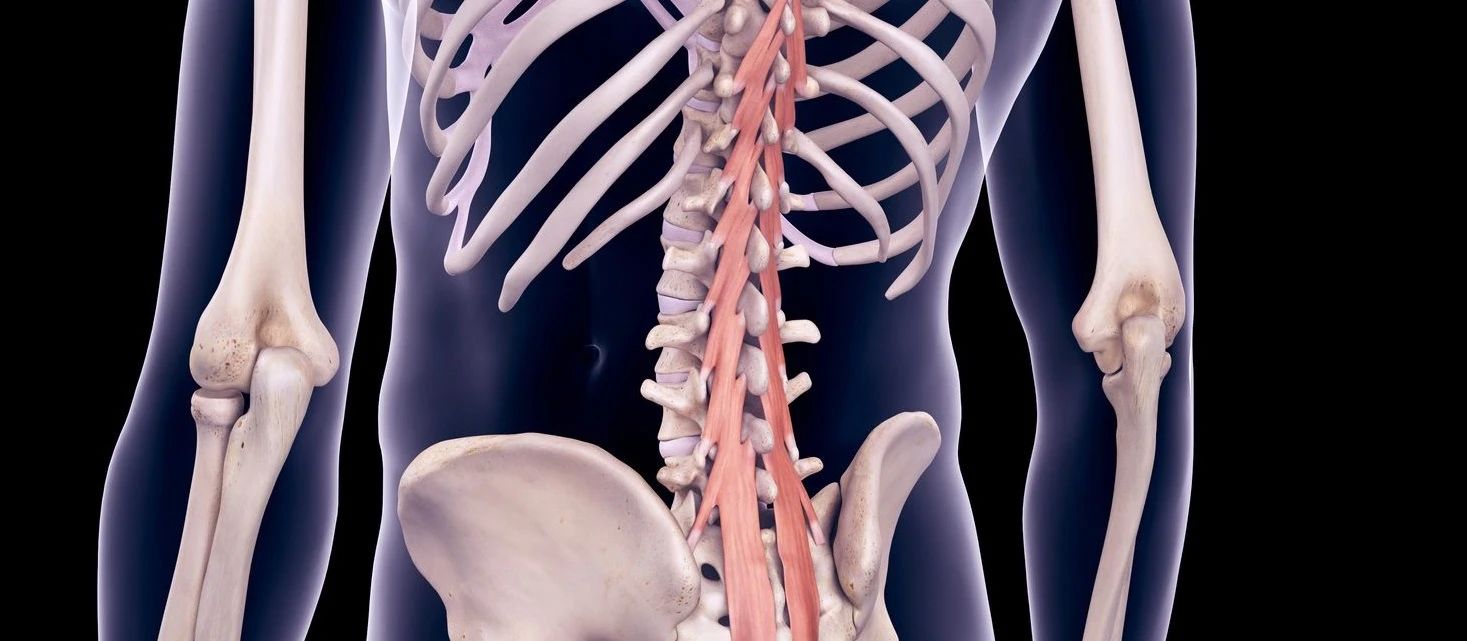

在研究腰椎肌肉穩(wěn)定性時,腰椎多裂?。∕F)的作用很明顯。MF解剖結(jié)構(gòu)如圖 2。

圖2:腰椎多裂肌的深層束,通??缭揭粋€單一的節(jié)段,它們“位于提供腰椎的本體感覺反饋的戰(zhàn)略性位置。”

中間束可能在控制節(jié)間運動方面發(fā)揮作用,而表面束能夠在頭尾方向上提供扭矩。

腰椎多裂?。∕F)是腰椎的最強穩(wěn)定肌,雙側(cè)多裂肌的協(xié)同作用,占據(jù)了脊柱中性區(qū)剛度的三分之二以上。